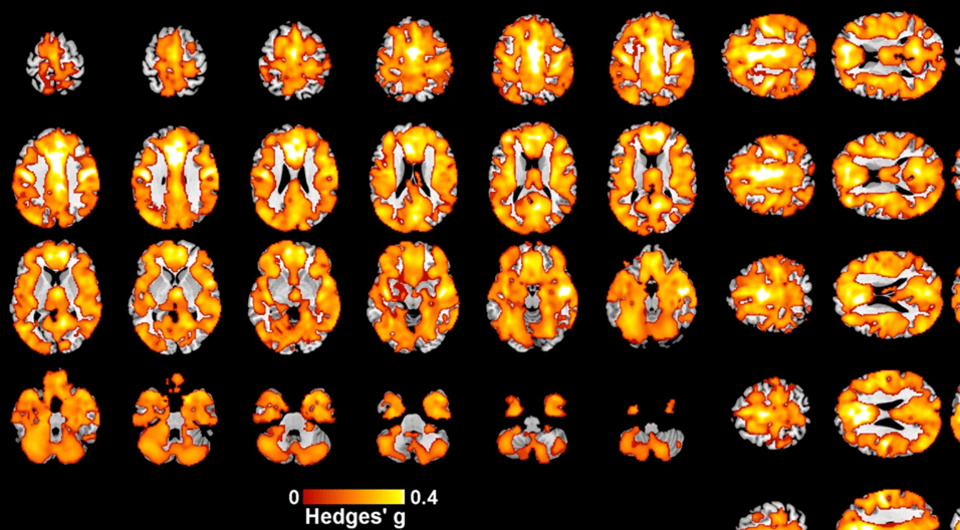

Ранние психозы связали со сниженным объемом серого вещества головного мозга

Ученые из пяти стран проанализировали магнитно-резонансные томограммы пациентов с ранними психозами и выяснили, что это состояние связано с повсеместным снижением объема серого вещества в коре больших полушарий головного мозга. Как сообщается в журнале Molecular Psychiatry, этот объем также зависел от возраста начала заболевания и дозы принимаемого хлорпромазина. При этом объем белого вещества изменялся в меньшей степени.